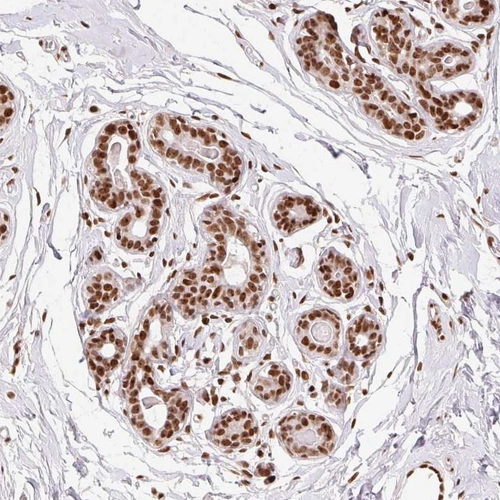

Immunohistochemical staining of human breast shows strong nuclear positivity in glandular cells.